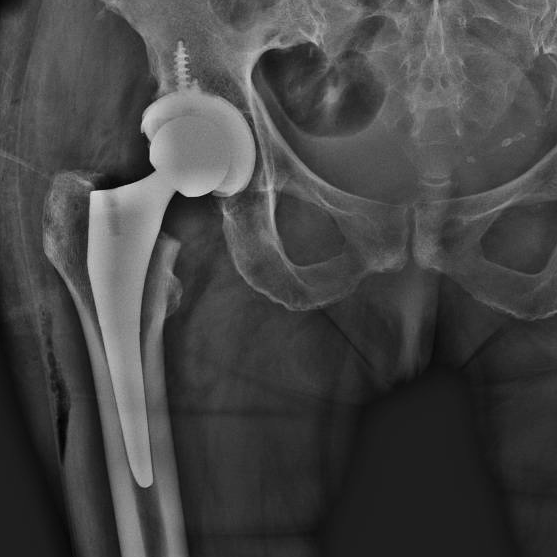

Se você precisa de uma artroplastia total do quadril e busca um procedimento de alta precisão, a cirurgia robótica pode ser a melhor opção...

A artroplastia total do quadril (ATQ) é um dos procedimentos mais eficazes na ortopedia para restaurar a mobilidade e aliviar a dor em pacientes...